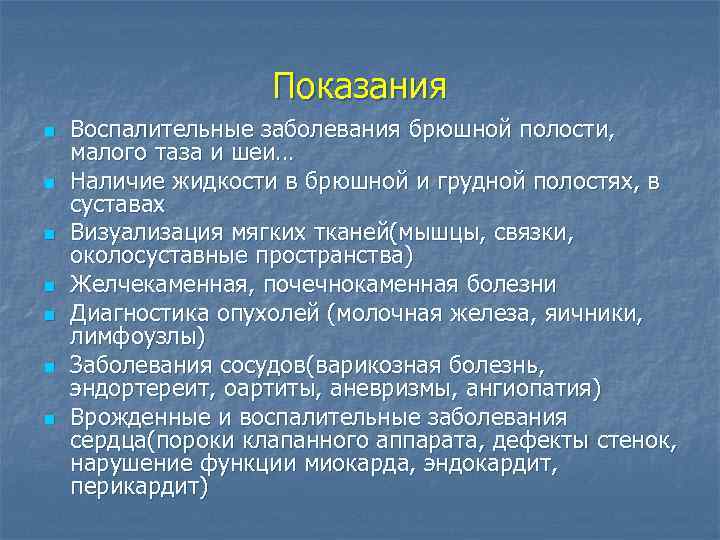

Показания n n n n Воспалительные заболевания брюшной полости, малого таза и шеи… Наличие жидкости в брюшной и грудной полостях, в суставах Визуализация мягких тканей(мышцы, связки, околосуставные пространства) Желчекаменная, почечнокаменная болезни Диагностика опухолей (молочная железа, яичники, лимфоузлы) Заболевания сосудов(варикозная болезнь, эндортереит, оартиты, аневризмы, ангиопатия) Врожденные и воспалительные заболевания сердца(пороки клапанного аппарата, дефекты стенок, нарушение функции миокарда, эндокардит, перикардит)